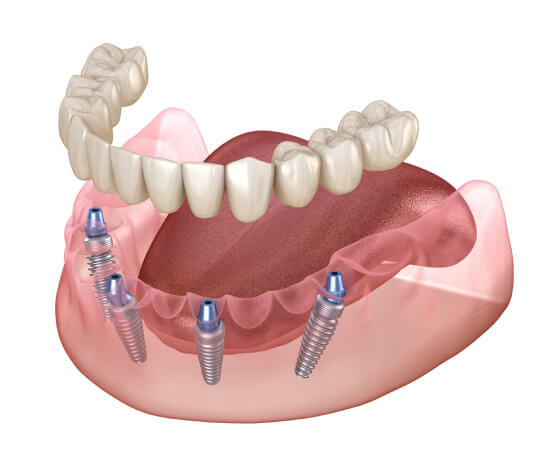

Dr. Randy Singh, Dr. Marty Sekand, Dr. Ken Jandoo and Dr. Steven Schneider of Love Your Smile Today have over 15+ years’ experience with the All-on-X dental implant treatment procedure. The All-on-X treatment concept was developed to provide edentulous (no teeth present) patients with an efficient and effective procedure to replace all of your missing teeth. The procedure uses only four to six dental implants to support the immediately loaded full-arch prosthesis or denture.

- The All-on-X dental implant procedure uses 4-6 implants, with back implants angulated to take maximum advantage of existing bone. Special implants were also developed that could support the immediate fitting of replacement teeth.

- With the All-on-X procedure, often no bone grafting is required. Qualified patients receive just four-six implants and a full set of new replacement teeth in usually just one appointment.